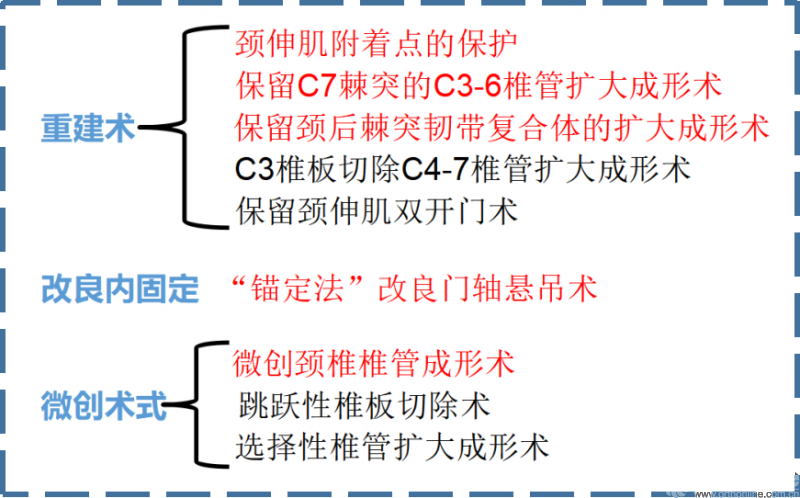

各种改良的椎板成形术或多或少提高了神经症状的改善率,同时减少椎板成形术后轴性症状成为学者们改良术式时共同努力的目标。目前术式改良主要涉及肌肉韧带重建、改良内固定和微创入路三个大方向。

①重建术式的部分解读

②改良内固定术式的部分解读

③微创术式的部分解读